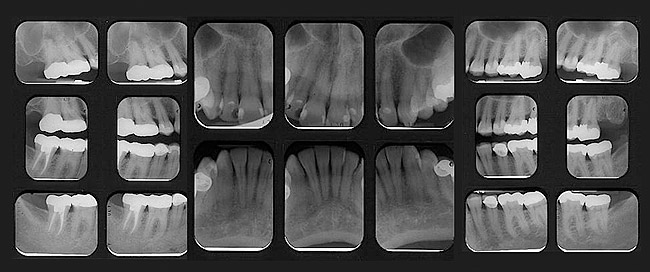

PARODONTAL: Evaluarea parodontală a evidenţiat adâncimi de sondare de 2-3mm în sextantele frontale şi de 2-5mm în cele posterioare. În regiunile laterale s-a observat o uşoară sângerare generalizată la sondare. Examinarea radiologică a obiectivat o pierdere osoasă orizontală generalizată uşoară spre moderată de 1-3mm. S-a descoperit un defect osos vertical pe faţa mezială a molarului 1.7. cu o adâncime de sondare asociată de 5mm (fig. 3). S-a stabilit un diagnostic parodontal de AAP tip II (parodontită uşoară).

BIOMECANIC: Examinarea radiologică a identificat patologie apicală la nivelul molarilor 2.7. şi 1.7. (fig. 3, 4). Era vizibilă o leziune radiologică difuză, mixtă (fig. 4) apical de 1.6. şi 1.5., având un aspect care sugera un chist mucos de retenţie.1 Clinic, dinţii 2.7. şi 1.7. s-au dovedit a fi devitali la testare, în timp ce 1.5. şi 1.6. erau vitali.

S-au constatat carii dentare active la nivelul 1.7., 4.6. şi 4.4. Dinţii 1.7., 1.6., 2.4.-2.7., 4.4., 4.7. prezentau restaurări cu adaptare defectuoasă. Dinţii 1.7.-1.5., 2.5.-2.7., 3.5.-3.7., 4.5.-4.7. au fost notaţi cu structură compromisă datorită dimensiunii, tipului şi profunzimii restaurărilor. În plus, segmentul dentar 3.2.-4.2. prezenta semne precoce de eroziune chimică la nivelul muchiilor incizale. Corespunzător 1.6. s-a obiectivat o exostoză osoasă pe versantul vestibular (fig. 5), generând o înălţime scurtă a coroanei clinice şi un compromis restaurator ulterior.